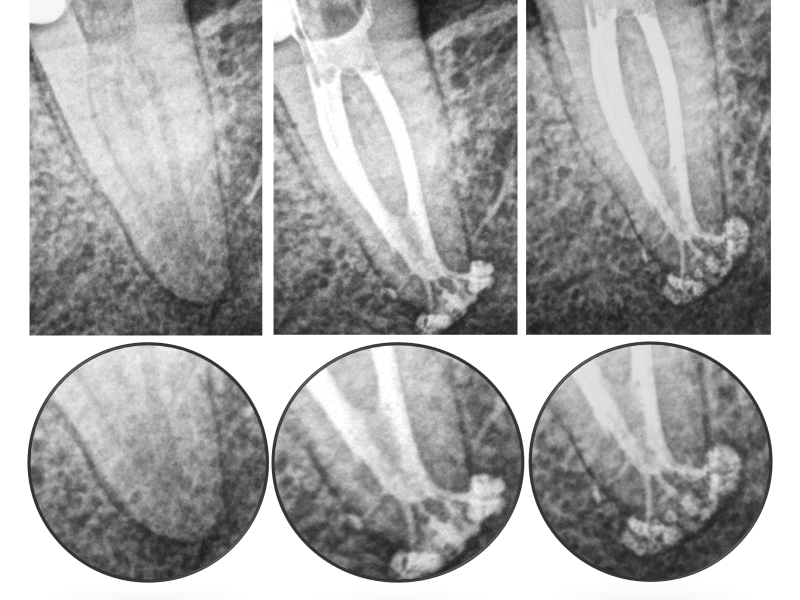

Apical Complex Anatomy with 1 Year Healing Evidence